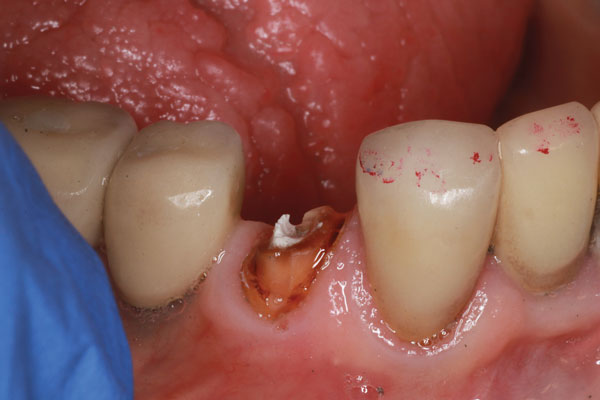

Un paciente se presentó con un diente roto (es decir, el diente No. 28) que requirió tratamiento de conducto. Hubo una pérdida significativa de estructura dental; por lo tanto, se consideró necesario un tratamiento posterior y central para sostener una corona (Figura 1). El paciente fue anestesiado y se excavó cualquier caries restante. Después de obtener, evaluar y medir una radiografía, se utilizó un taladro para eliminar aproximadamente dos tercios de la longitud del material de obturación del conducto radicular (Figura 2). Se tomó otra radiografía para confirmar que la profundidad alcanzada era correcta. A continuación, se probó primero el sistema de poste ajustable único (Splendor SAP, Angelus) sin el manguito para determinar si estaba completamente asentado (Figura 3). Luego se probó con el manguito y se consideró que encajaba bien (Figura 4).

Imagen 4 La prueba del poste y la funda Splendor SAP muestra un ajuste excelente.